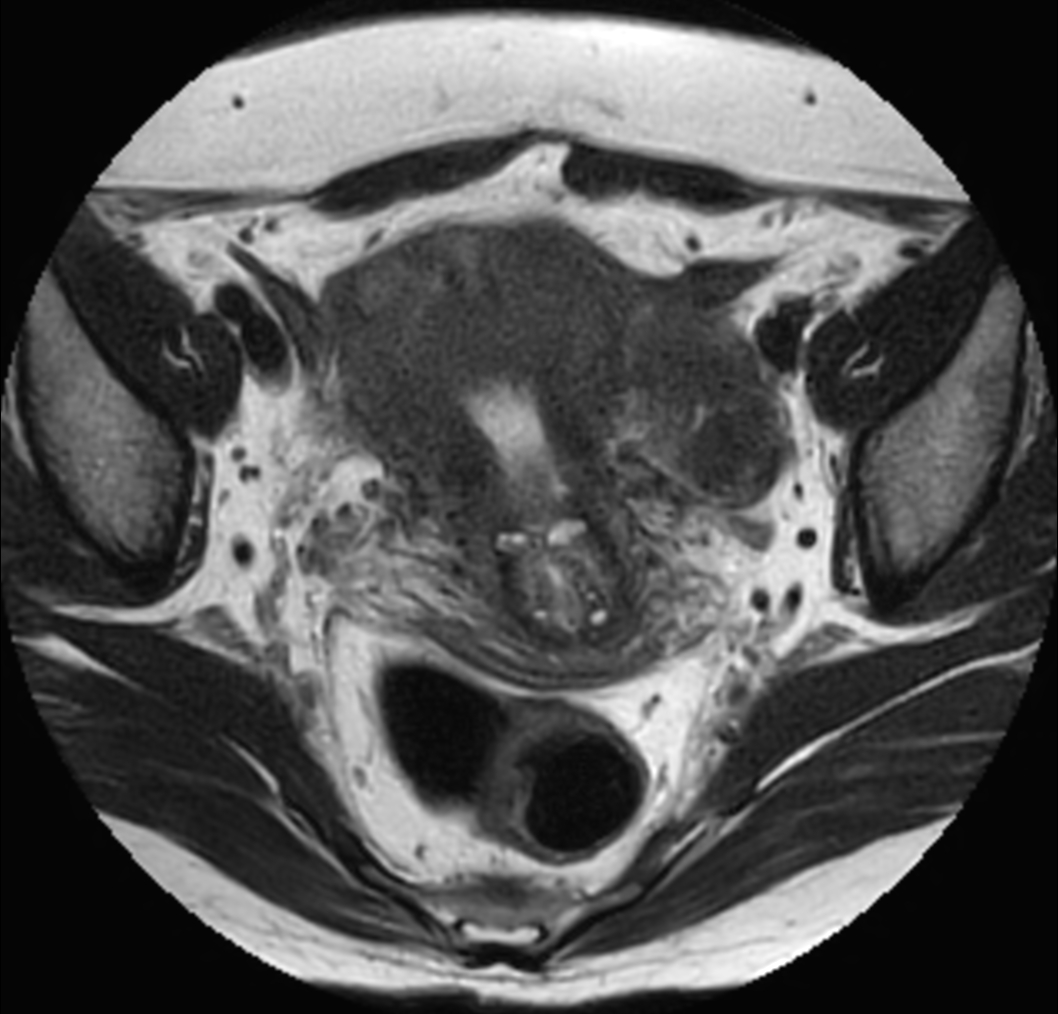

Axial MultiVane XD - T2w TSE